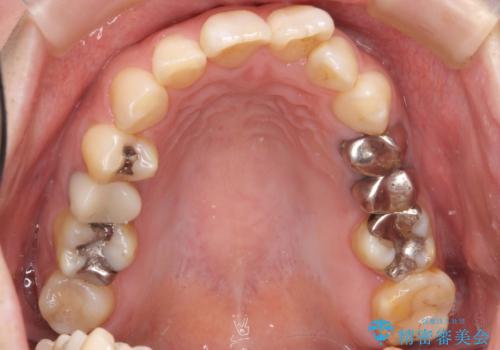

- 前歯の歯並びが気になることを主訴に来院された患者様です。

顎が小さく歯を並べるためのスペースが足りないため、

上下の前歯の歯と歯の間をすく処置(ディスキング)を行いました。

矯正後、右上5左上45セラミッククラウン・右下65左下5セラミックインレーによる補綴治療を行いました。

なお、左下の奥歯(左下7)は状態が悪く保存不可能と判断し矯正前に抜歯しております。